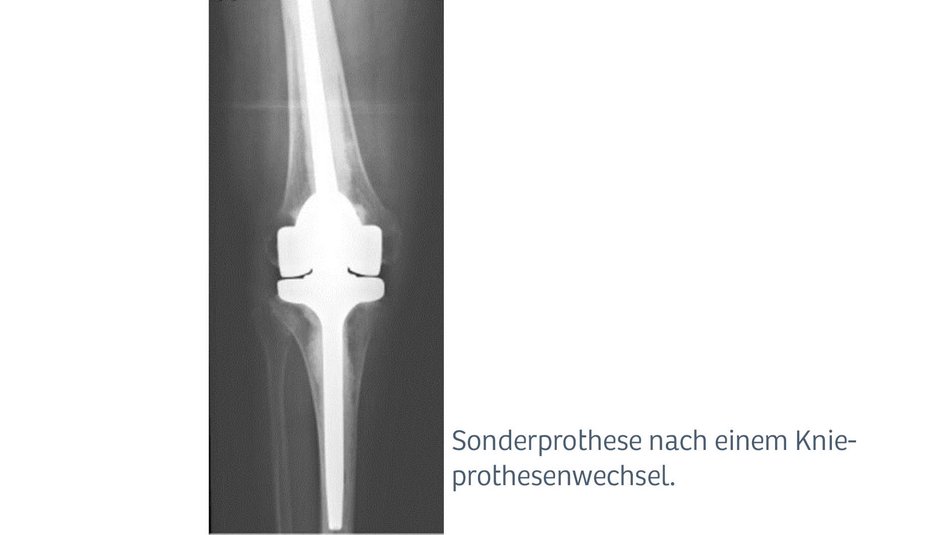

Bei komplexen Operationen (bspw. Infektionen, Knochenbrüchen bei liegender Prothese oder Wechseloperationen) ist eine besondere Expertise gefragt. In diesen Fällen werden meist aufwändige Spezialprothesen oder Sonderanfertigungen verwendet.

Die Infektion einer Gelenkprothese gehört zu den seltenen, aber gefürchteten Komplikationen. Zur Behandlung ist ein hohes Maß an Erfahrung, ein konsequentes Vorgehen und ein etabliertes Behandlungskonzept unabdingbar. Bei uns arbeitet ein interdisziplinäres Team aus Mikrobiologie, verschiedensten Laboren, ausgebildeten Antibiotikaspezialisten, Intensivmedizin und erfahrenen Operateuren, „Hand in Hand“. So können gute Erfolge in der Behandlung von Protheseninfektionen erzielt werden. In diesen Fällen werden meist aufwendige Spezialprothesen oder Sonderanfertigungen verwendet.

Aufgrund der älter werdenden Gesellschaft nehmen Knochenbrüche wie Schenkelhalsfrakturen oder Knochenbrüche bei liegender Prothese (periprothetische Fraktur) zu. Es handelt sich dabei um sehr schwere Verletzungen beim meist älteren und oft vorerkrankten Patienten Diese Verletzungen sind für die Patienten sehr belastend und stellen Arzt und Patienten oft vor große Herausforderungen. Eine enge Zusammenarbeit mit anderen Fachabteilungen wie der Inneren Medizin, Geriatrie und Intensivmedizin ist oft notwendig. Bei der Versorgung dieser Verletzungen kommen oft aufwändige Sonderprothesen zum Einsatz. Defekter Knochen wird aufwändig rekonstruiert oder wenn nötig durch Spezialimplantate ersetzt.